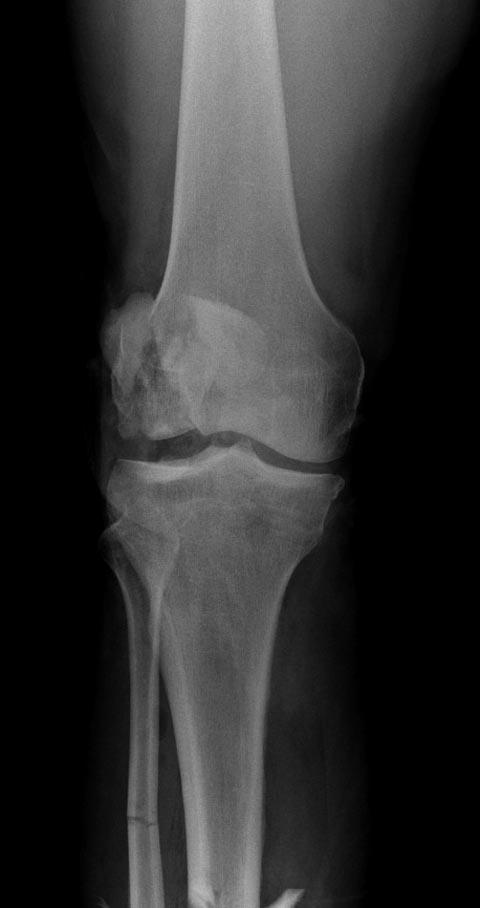

Здесь представлен посттравматический дефект латерального мыщелка и

лечение аллографтом.

Вложение не в текстовом формате было извлечено…

Имя     : Medial Tibial plateau 01.jpg

Тип     : image/jpeg

Размер  : 40173 байтов

Описание: отсутствует

Url     : http://weborto.net:8080/pipermail/ortho/attachments/20141113/94e46382/attachment-0005.jpg